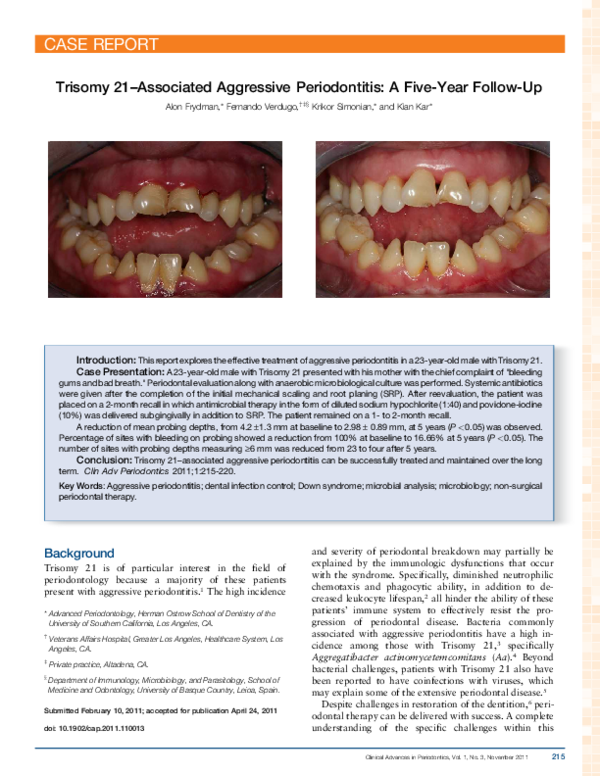

(PDF) Trisomy 21Associated Aggressive Periodontitis A FiveYear Trisomy 21 Vsd chromosomal disorders caused by absent or duplicated chromosomes include trisomy 21 (down syndrome), 22q11 deletion (digeorge syndrome), and 45x deletion (turner syndrome). Down syndrome, trisomy 21, congenital heart disease, congenital heart surgery, perioperative. From 5% to 8% of congenital heart disease patients have a chromosomal disorder. in this review, we discussed the risk of aneuploidy and the outcome. Trisomy 21 Vsd.